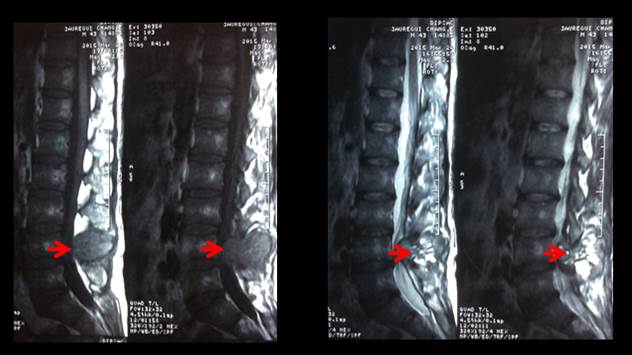

En la RM columna lumbosacra (figura 4) se observó una lesión estenosante del canal raquídeo a nivel de L4 – L5, deformación del arco posterior de L4 por una estructura heterogénea con múltiples formaciones hiperintensas de diversos tamaños siendo la mayor de 10 mm y que ocasionaba efecto de masa desplazando los tejidos blandos adyacentes.